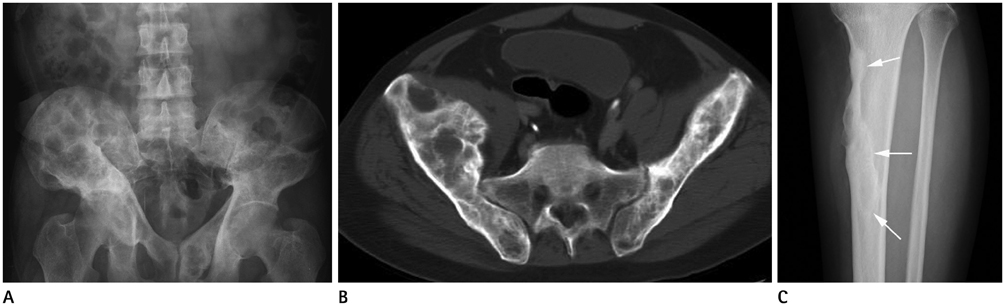

Systematic Approach of Sclerotic Bone Lesions Basis on Imaging Findings

- Sclerotic bone lesions are common, but there are diverse groups of tumors and non-tumorous lesions. Although plain radiograph and computed tomography can reveal important characteristics of these lesions, diagnosis is often challenging for radiologists. A systematic approach and familiarity with the imaging features of various sclerotic bone lesions may be greatly helpful for eliminating in the differential diagnosis. This review describes the systematic approach to diagnosing sclerotic bone lesions based on imaging findings.